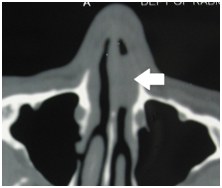

All the patients underwent routine laboratory investigations that are required for surgical management. Except one patient, all patients presented with epistaxis and for this patient CT scan of nose and paranasal sinuses was done and it showed a soft-tissue mass in the anterior part of the left nasal cavity (Figure 4).

Figure 4 CT scan picture showing soft-tissue mass [arrow] in the anterior part of the left nasal cavity.

CT scan is not usually required in cases of rhinosporidiosis. However, when a mass completely obstructs the nasal cavity, CT can be helpful in determining its extent. Surgical excision with cauterization of the base is the treatment of choice for rhinosporidiosis. Bleeding during surgery is usually profuse and can be life-threatening. Therefore, establishing a diagnosis before surgery is important.6